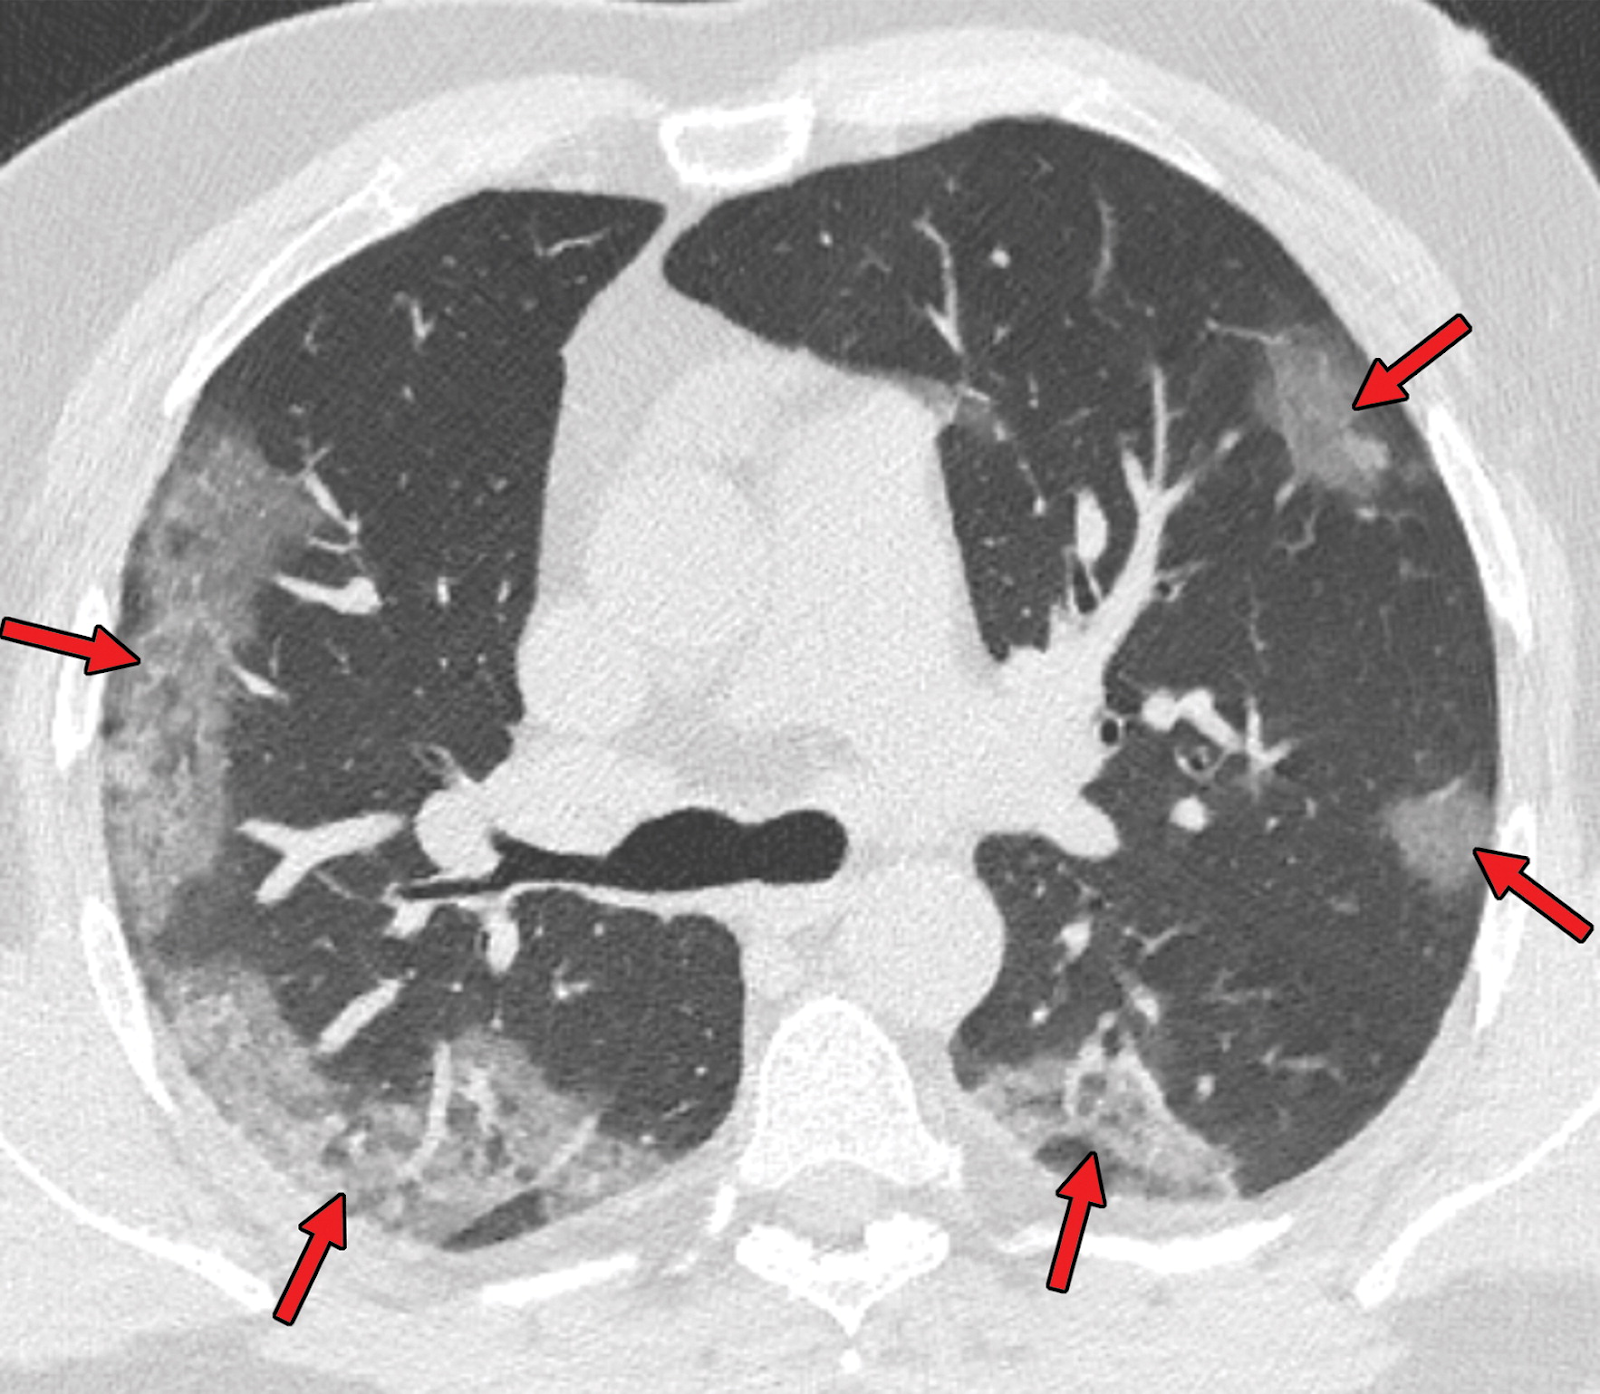

De exames complementares laboratoriais podemos solicitar um hemograma com hemocultura, cultura de escarro, testes de Influenza A e B juntamente com o de Vírus Respiratório Sincicial e o RT-PCR para o Coronavírus. Na investigação de imagem, o padrão-ouro é a Tomografia Computadorizada de alta resolução (TCAR) de tórax. Na prática, infelizmente, a TCAR não estará sempre disponível, sendo o Raio-X simples seu substituto. O achado será o padrão de vidro fosco por infiltrado intersticial. Veja abaixo: